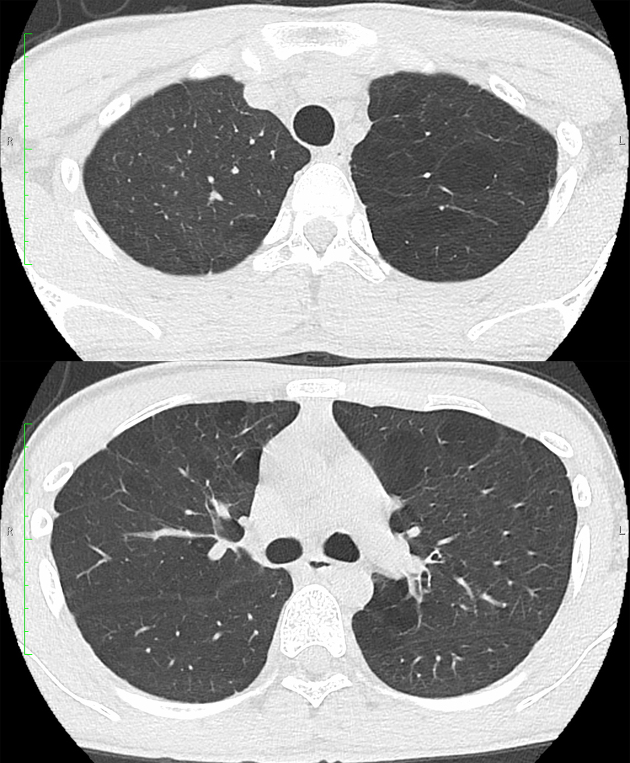

A Case of Asymptomatic Juvenile Emphysema.